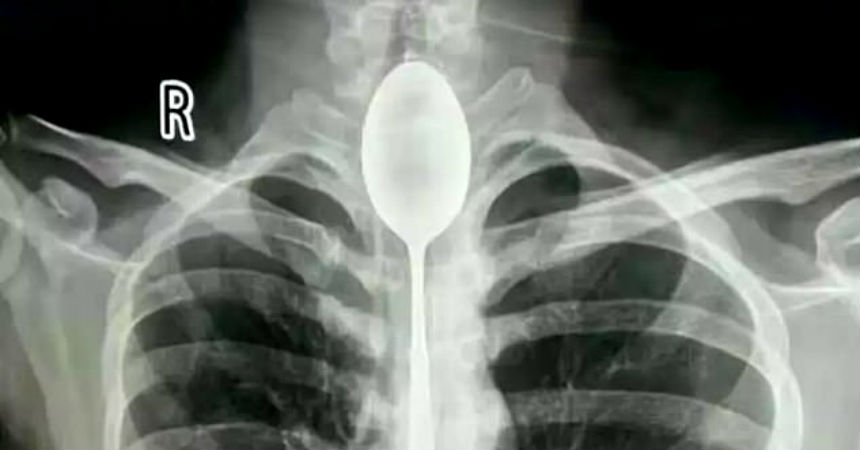

Es lo que ocurrió con un hombre de 26 años que llegó al Hospital General de Xinjiang Meikuang, en China, con una cuchara de 20 centímetros atorada en el esófago. Lo más curioso es que el objeto lo tenía alojado hace un año en su interior, según señala Daily Mail.

«Quedé impactado. Nunca he tenido algo así», dijo Yu Xiwu uno de los médicos que trató al paciente, el cual ya tenía complicaciones en su cuerpo lo que le había provocado una infección en esófago.

Según reconoció el paciente, de apellido Zhang, todo se debió a una apuesta que hizo con unos amigos, donde aseguró que era capaz de tragarse una cuchara. El hombre cumplió su palabra y lo hizo. El problema es que luego no pudo sacársela y anduvo un año con el objeto dentro de su cuerpo.

El hombre señaló que no había acudido antes al hospital porque en ningún momento le había molestado para hablar o comer. Sin embargo, un día recibió un golpe en el pecho lo que le provocó complicaciones derivadas a la cuchara que tenía en esófago.

Afortunadamente los médicos pudieron extraer la cuchara y el hombre se recupera satisfactoriamente.

Fotos: Hospital General de Xinjiang Meikuang